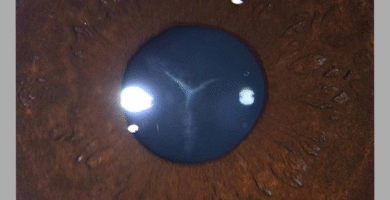

Understanding Key Signs in Rhegmatogenous Retinal Detachment